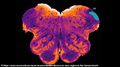

| مخطط الحبل الشوكي. | |

في 23 نوفمبر 2018 أعلن العلماء عن اكتشاف منطقة مختبئة Endorestiform Nucleus في المخ، يمتاز بها البشر، وقد تساعد في علاج مرض پاركنسون ومرض العصبون الحركي. عثر الأستاذ جورج پاكسينوس من مركز أستراليا للعلوم العصبية هذه المنطقة المختبئة، والمسماة Endorestiform Nucleus، وحسب قوله فإن: هذه "المنطقة مثيرة للاهتمام لأنها تبدو غير موجودة في المكاك الريسوسي والحيوانات الأخرى التي درسناها". تقع هذه المنطقة بالقرب من التقاء الحبل الشوكي بالمخ، ويقتصر وجودها على المخ البشري. تجمع هذه المنطقة بين المعلومات الحسية والحركية لتحسين وضعية الجسم، والتوازن، والحركات الدقيقة. وعلى الرغم من عدم المعرفة الدقيقة لوظيفة هذه المنطقة إلا أنه بالنظر إلى الجزء الذي تقع فيه داخل الدماغ، فمن المرجح أنها تلعب دوراً رئيسياً في التحكم الحركي الدقيق. [5]